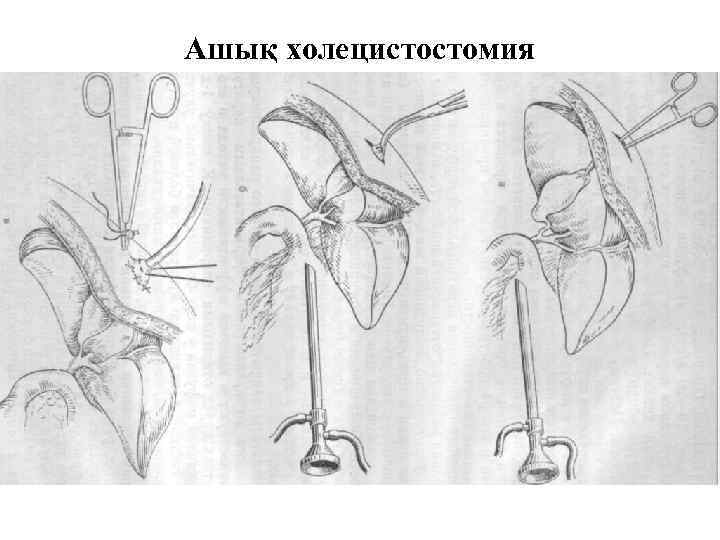

Ашық холецистостомия